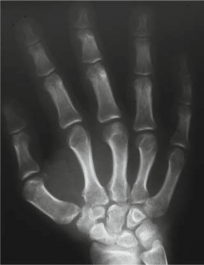

Additional Radiographs (Knees and Ankles):

To assess the widespread nature of MED, radiographs of other commonly affected joints were obtained.

* Knees: Revealed widened and irregular epiphyses of the distal femora and proximal tibiae. Patella alta was noted. Significant joint space narrowing was observed in the patellofemoral and medial tibiofemoral compartments. Mild valgus deformity was confirmed.

* Ankles: Demonstrated flattened and irregular talar domes, contributing to a widened ankle mortise and evidence of subtalar arthritis.

* This image typically represents an anteroposterior view of the knee, showcasing the irregular and flattened epiphyses, potentially widened and disorganized growth plates (if skeletally immature), and early degenerative joint changes consistent with the manifestations of Multiple Epiphyseal Dysplasia.